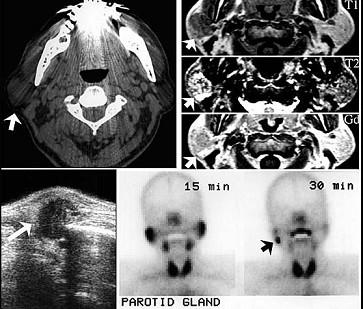

问题 60岁男性,左耳垂下无痛性肿物缓慢长大四年,局部有胀感。检查见肿块位于腮腺后下极,表面光滑,质中偏软,不可压缩,与皮肤无黏连。影像检查结果如图。最可能的诊断是()

选项 A.腮腺多形性腺瘤 B.腮腺沃辛瘤 C.腮腺内淋巴结炎 D.腮腺血管瘤 E.腮腺囊肿

答案 B